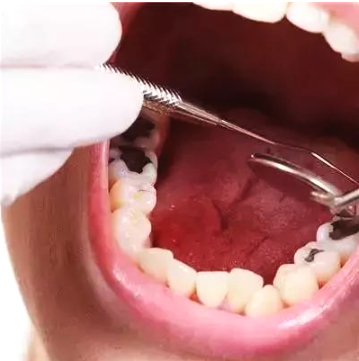

3、易发龋齿和牙龈炎

不用的那一侧牙齿由于长期缺乏食物摩擦,而在牙齿间堆积大量的牙垢和牙石,容易发生龋齿并引发牙龈炎、牙周炎。